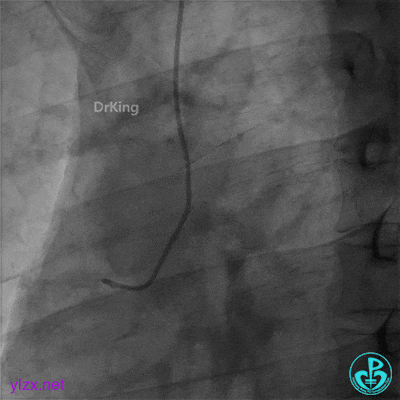

造影示右冠脉近段完全闭塞。

导丝通过,沿指引导管冠脉内注射用重组人TNK组织型纤溶酶原激活剂8mg,球囊扩张后,出现再灌注心律失常,“让子弹飞一会”,等待,未造影,5分钟后造影示右冠脉中段可见大量血栓,前向血流TIMI 2级。